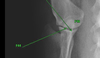

19

Q

F21

A

Head of Radius

20

Q

F22

A

Medial styloid process of radius

21

Q

F24

A

olecranon of ulna

22

Q

F25

A

lateral styloid process of ulna

23

Q

F26

A

anconeal process of ulna

24

Q

F27

A

trochlear notch of ulna

25

F28

medial coronoid process of ulna

26

F29

lateral coronoid process of ulna

27

F30

radial fossa/notch of ulna

28

F31

nutrient foramen of ulna

29

F33

radial carpal bone

30

F34

ulnar carpal bone

31

F33

radial carpal bone

32

F34

ulnar carpal bone

33

F35

I-IV carpal bones

34

F37

accessory carpal bone

35

F36

local sesamoid

36

F38

I - V metacarpi

37

F39

proximal/middle/distal phalanges

38

F40

ungual process

39

F41

ungual crest

40

F42

Dorsal and Palmar sesamoid bones

41

F42

Palmar sesamoid bone

42

F50

mineralized clavicular tendon (dog)

43

F44

scapulohumeral joint

44

F45

elbow (humeroulnar, humeroradial radioulnar)

45

F46

carpal (radiocarpal, intercarpal, carpometacarpal)

46

F47

metacarpophapangeal joint

47

F48

interphalangeal (proximal, distal)

48

F49

clavicle (cat)